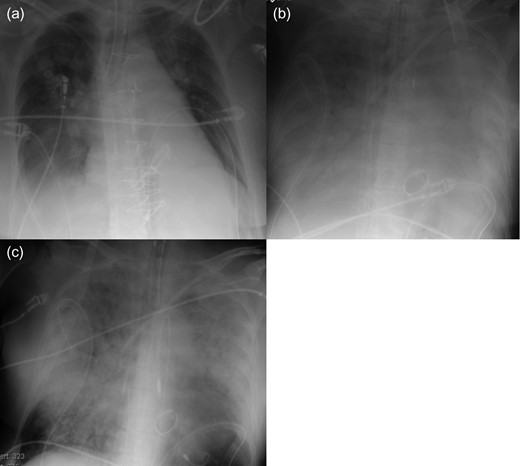

A 72-year-old man with a huge ventricular aneurysm due to a previous myocardial infarction in the anterior wall experienced an acute large myocardial infarction in the posterior wall due to total occlusion of the right coronary artery. Despite emergency coronary intervention at a regional hospital, his condition worsened and severe CS developed. After an emergency call, our ECLS team implanted ECLS percutaneously through the right femoral vessels, then the patient was transferred to our hospital. His condition rapidly stabilized. His left ventricular ejection fraction was ~20%, with a giant ventricular aneurysm on the anterior wall, akinesia of the posterior wall, and moderate mitral valve regurgitation (MR). On Day 7, chest radiography indicated that PE had worsened (Fig. 1a and b). Echocardiography revealed new onset of a small ventricular septum perforation that had not been detected by daily echocardiography. On Day 8, the Impella system was percutaneously implanted through the left femoral artery for direct unloading of the LV as therapy for PE. After Impella implantation, PE considerably improved (Fig. 1c). The flow from the Impella system was 2.0 l/min, whereas the flow from ECLS remained unchanged at 6 l/min; therefore, he had more output than before Impella implantation. However, his general condition had worsened due to sepsis and he died 2 days after Impella implantation.

Radiography of Patient 1. (a) After ECLS implantation. (b) Before Impella implantation. (c) Two days after Impella implantation.